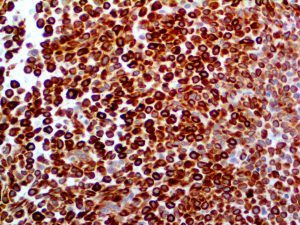

The first cytokines released are interleukin 1β (IL-1β) and tumor necrosis factor-α (TNF-α), which attract a variety of circulating white blood cells (WBCs) to the infection site, including neutrophils, monocytes, macrophages, and natural killer (NK) cells. This response, along with the antipathogenic chemicals released by these cells (i.e., complement), comprise the innate immune response. These cells directly attack the invading pathogen and also release additional cytokines, chief among them interleukin-1 and 6 (IL-6). IL-6 is essential for invoking the adaptive immune response, which calls T-cells, B-cells, and T helper (Th) cells to the infection site. IL-6 also stimulates further recruitment, proliferation and activation of macrophages.

It is the ICU physician who is most likely to witness one of the deadliest manifestations of the abnormal immunological response, the cytokine storm syndrome (CSS). This response is also referred to by some as the cytokine release syndrome (CRS). CSS is characterized by continuous activation and expansion of macrophage and lymphocyte populations, which secrete large amounts of cytokines, causing the cytokine storm. This massive cytokine release is akin to hemophagocytic lymphohistiocytosis (HLH) disease, a syndrome characterized by initial unchecked and persistent activation of cytotoxic T lymphocytes and NK cells.